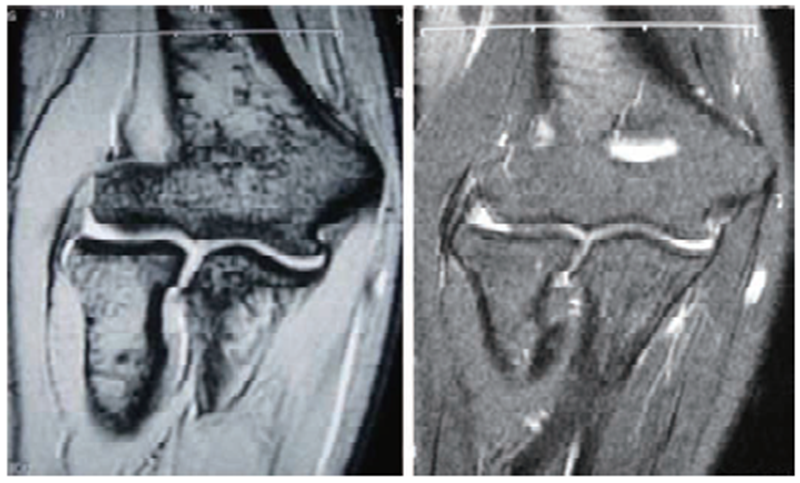

(2)MRI检查

MRI检查可见T1和T2信号增强,提示肌腱肥厚。部分患者合并出现关节积液、肱桡关节滑膜增生等表现。